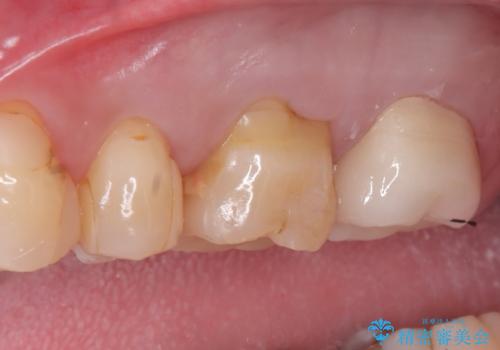

- 患者様は、左上7のメタルインレー(銀の詰め物)の見た目が気になるとのことで来院されました。診察したところ、メタルインレーの下にむし歯の再発リスクがあることも確認。より審美性と耐久性を高めるため、メタルインレーを除去し、セラミッククラウンで補綴する治療計画を立てました。

メタルインレーを丁寧に除去し、歯の状態を確認。その後、精密な形成を行い、適合性の高いセラミッククラウンを装着しました。セラミッククラウンは天然歯に近い見た目で、美しさだけでなく強度や機能性にも優れているため、患者様にも「自然な仕上がりで違和感なく噛める」と大変ご満足いただきました。